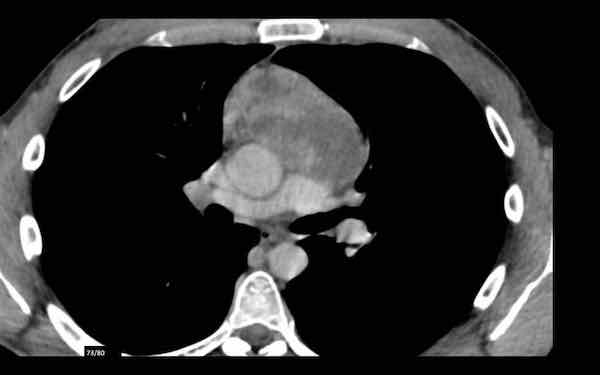

Các hình ảnh này của một phụ nữ 65 tuổi có tiền sử mắc bệnh Graves, một rối loạn tự miễn liên quan đến tình trạng cường chức năng tuyến giáp.

CT được thực hiện vì lý do ho ra máu.

Hình ảnh

Có một tuyến ức to lớn, cồng kềnh chứa mô mỡ đại thể.

Đây là hình ảnh điển hình của tăng sản tuyến ức.

Tăng sản tuyến ức trong bệnh Graves có liên quan đến tình trạng dư thừa hormone tuyến giáp và kháng thể kháng thụ thể thyrotropin.

Tình trạng này thường cải thiện sau khi điều trị thành công bệnh Graves.